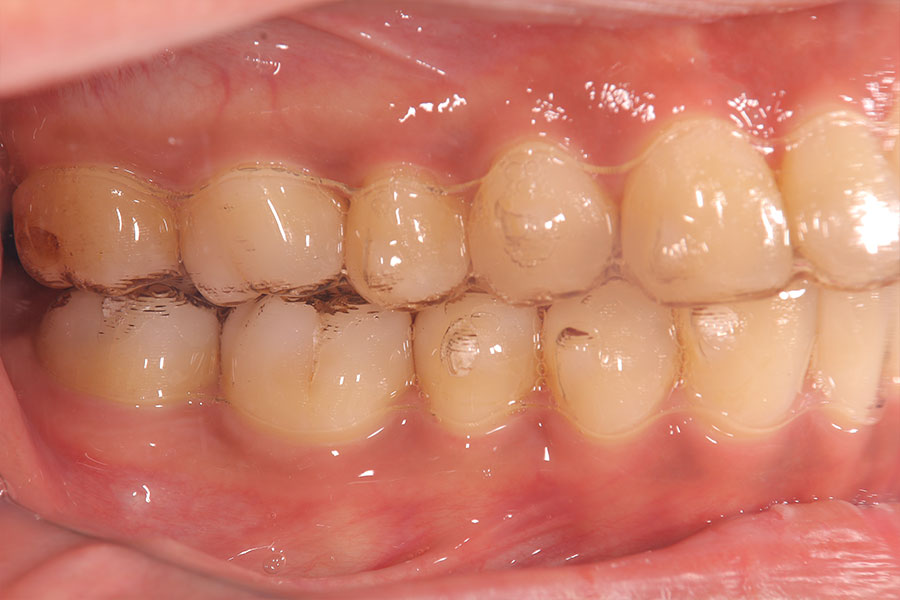

Before -側面-

After -側面-

| 施術内容 | ワイヤー矯正から、目立ちにくくメタルフリーなインビザラインへ変更しました。 金属アレルギーの不安が軽くなり、取り外しできることで清掃性も向上。見た目も自然で、治療中のストレスが少ない矯正方法です。 |

|---|---|

| 治療期間 | 2年間 |

| 費用 | インビザラインフル 767,800円 リテーナー 30,000円 |

| リスク・副作用 | 治療にともない、歯の破折や歯質の削合、場合によっては抜歯が必要となることがあります。また、金属や補綴物を除去する際に、完全に除去できない場合もあります。 |